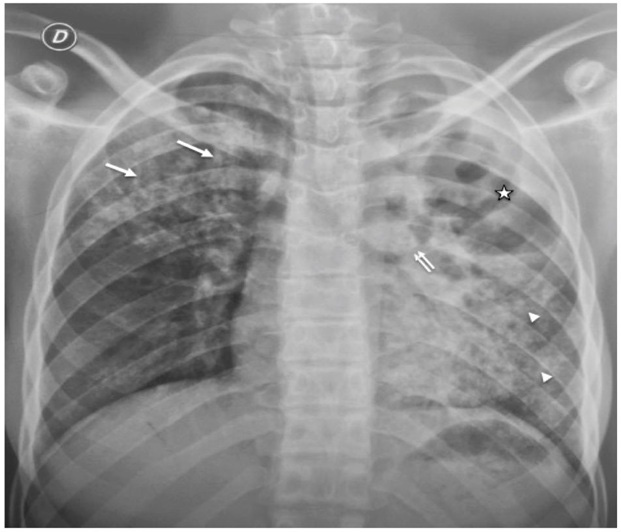

Figure 1: Chest X-ray of a 15 years old girl showing an interstitial syndrom:

- a vast cavern of the lingula (star) with a drainage bronchus (double arrow)

- a right apical infiltrate (arrow)

- and a left basal milial aspect (arrowhead).